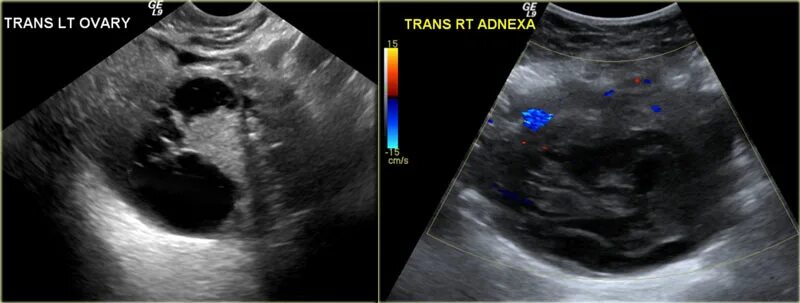

Солидное образование форум